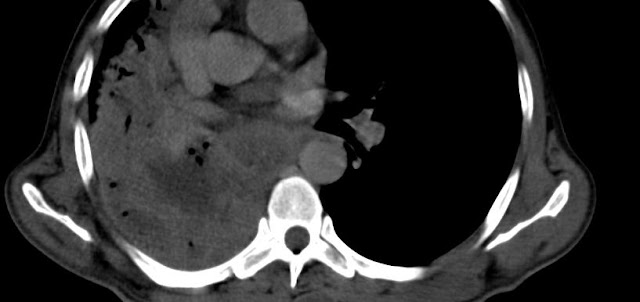

Necrotic Right Hilar mass

Necrotic right hilar mass lesion with invasion in to the right lower lobe bronchus causing complete collapse of right middle and lower lobe.